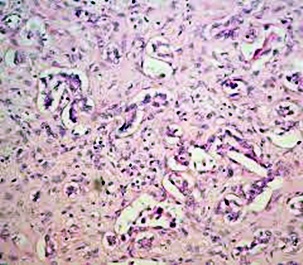

황달의 원인

황달이 생기는 이유는 담즙색소라고 알려진 빌리루빈이 과도하게 생기기 때문입니다. 빌리루빈은 우리 몸의 오래된 적혈구가 파괴되면서 생기는 물질인데요. 이 물질은 담즙에 녹아서 우리 몸의 배설물과 함께 배출이 되는 것이 정상적이지만 빌리루빈의 과잉생산이나, 간의 장애, 간세포나 담도의 손상에 의해 빌리루빈이 역류할 경우 발생된다고 합니다.